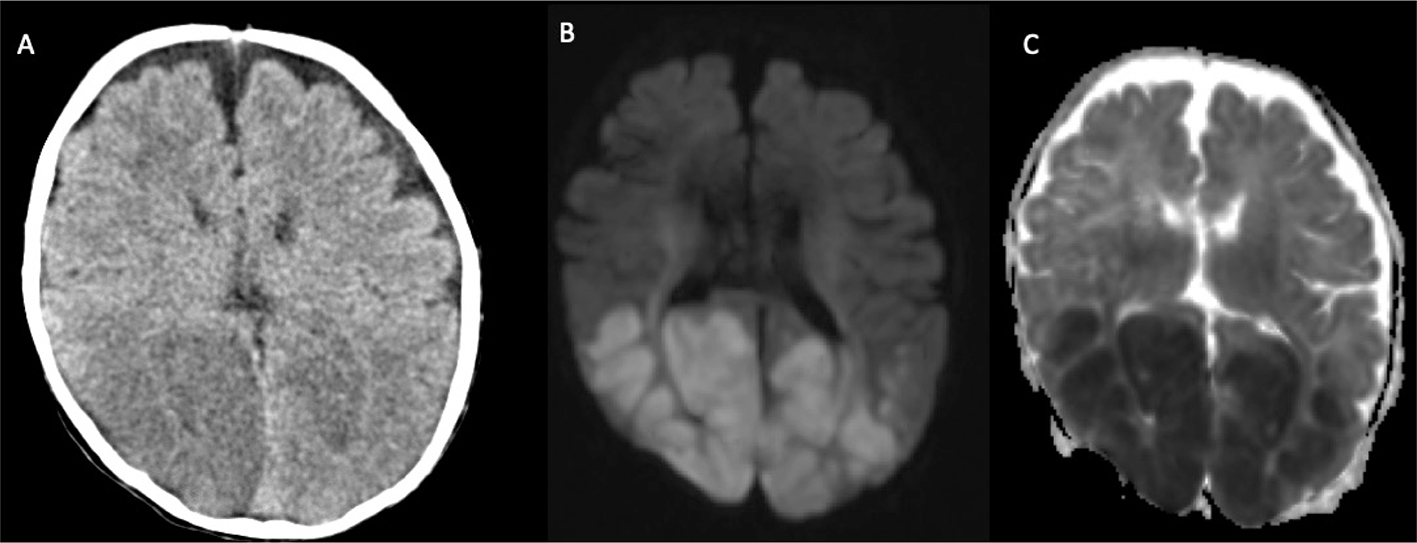

Although CT is often the first imaging modality performed, MR is generally preferred for its greater sensitivity, specificity, tissue contrast, and non-reliance on ionizing radiation or, in most cases, exogenous contrast agents. CT is nevertheless sensitive for acute intracranial hemorrhage in the acute setting. Cerebral infarction in the neonate has a similar appearance to that in the older child or adults, manifesting as a well-defined region of hypoattenuation in an arterial distribution (Figure 4), although small lesions can be difficult to identify on routine imaging due in part to unmyelinated brain masking subtle hypoattenuation. Additionally, certain areas in the posterior temporal and occipital cortices can have low attenuation on CT in normal infants and the risk for false positive classification of stroke merits circumspection. The “hyperdense artery sign” representing acute intraluminal thrombus is infrequently observed in neonates, and may relate to varying clot compositions, including potential differences in the presence, concentration, or composition of red blood cells and iron within the heme moiety of hemoglobin (45).

Fig 4

Figure 4. A 14-day-old boy with seizures. Axial non-contrast CT image showing unilateral diffuse hypodensity in the right PCA distribution (arrows). Case courtesy of Dr. Tamara Feygin, Department of Radiology, Children’s Hospital of Philadelphia.